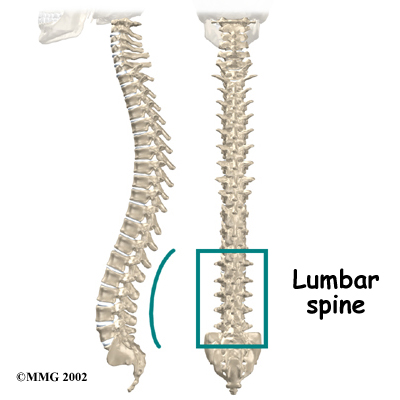

The human spine is formed by 24 spinal bones, called . Vertebrae are stacked on top of one another to form the spinal column. The spinal column gives the body its form. It is the body's main upright support. The section of the spine in the lower back is known as the .

The lumbar spine is made up of the lower five vertebrae. Doctors often refer to these vertebrae as L1 to L5. These five vertebrae line up to give the low back a slight inward curve. The lowest vertebra of the lumbar spine, L5, connects to the top of the sacrum, a triangular bone at the base of the spine that fits between the two pelvic bones. Some people have an extra, or sixth, lumbar vertebra. This condition doesn't usually cause any particular problems.